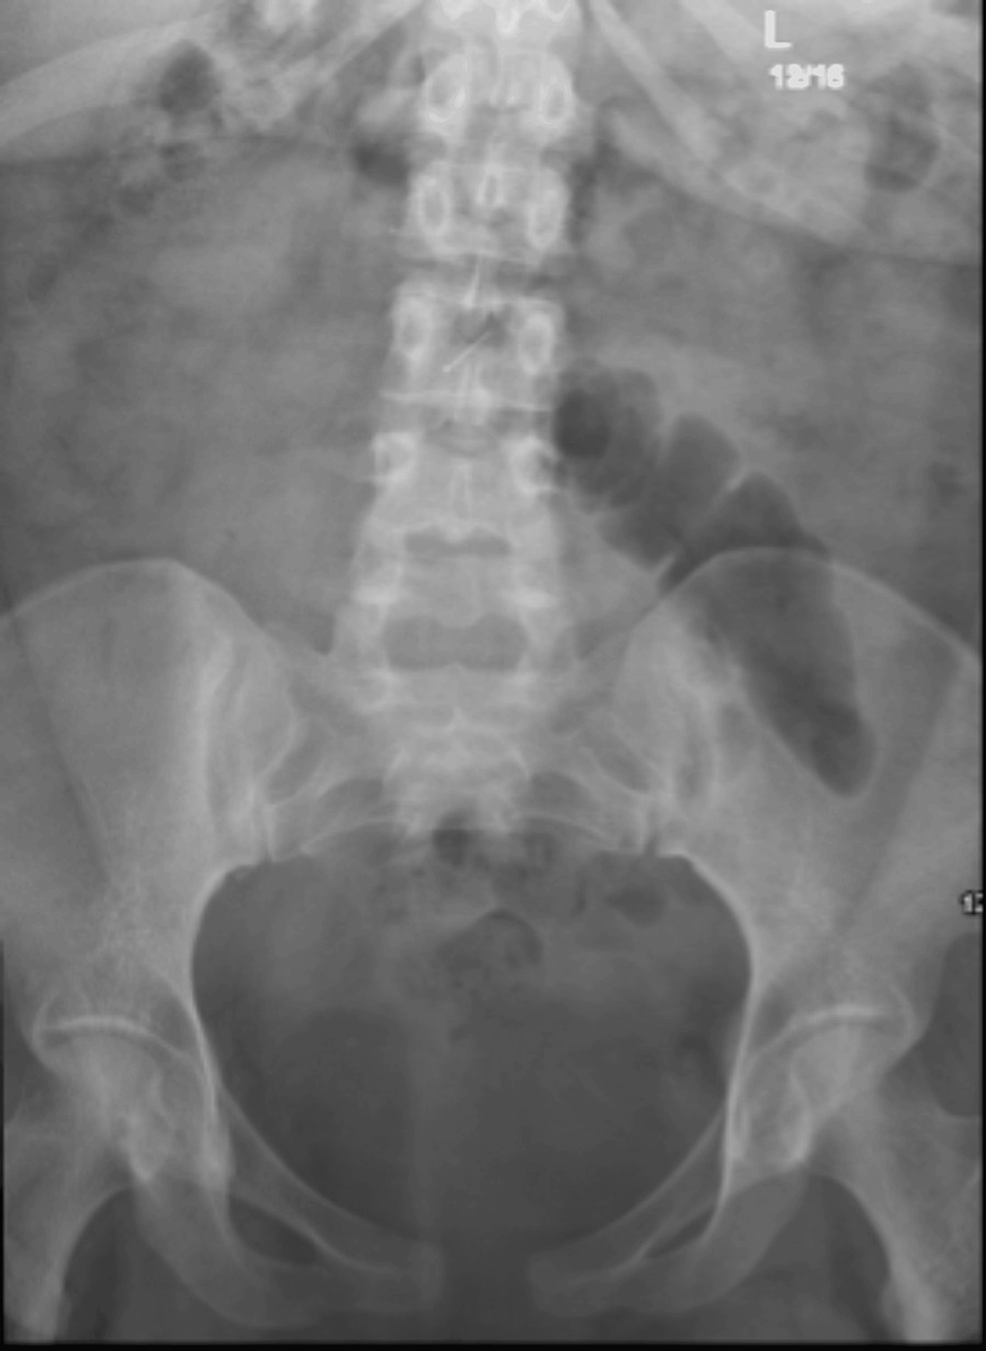

Computed tomography scan and resonance imaging showing Epidural Catheter Broke Off In Back Visualization of retained catheter is difficult. Catheter breakage is a recognised complication of epidural anaesthesia, often attributed to trauma on insertion or excessive. The epidural catheter was localized in the right paraspinal gutter and pulled out by using a blunt nerve hook. Hence, the decision was taken to remove the catheter, but as the catheter was being pulled off along. Epidural Catheter Broke Off In Back.